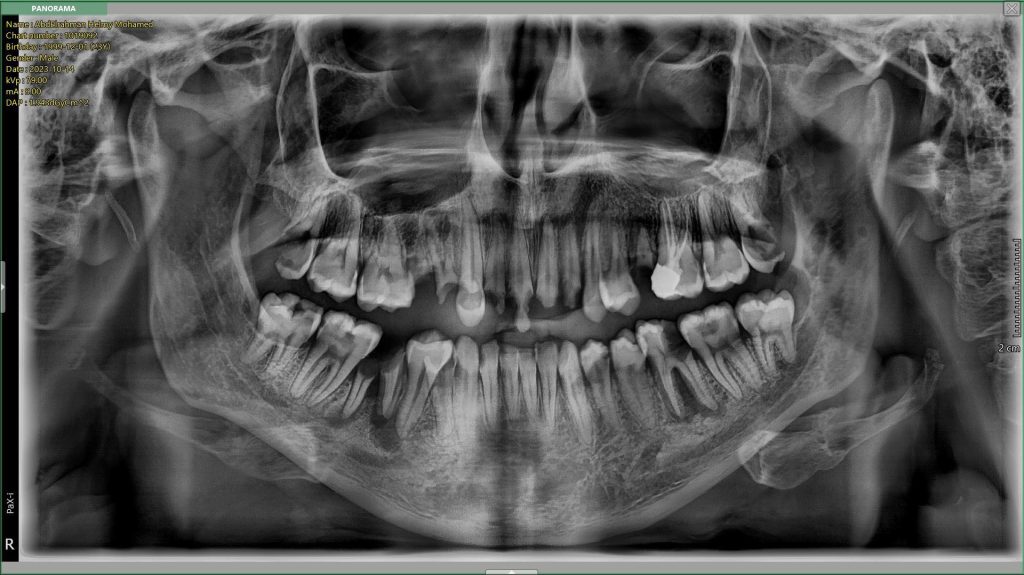

By the help of cephalometric analysis, the patient diagnosed as “Skeletal Class II”; Due to retuded mandible ( SNA= 84, SNB= 78, ANB= 5.92)

The patient suffered from Skeletal midline shift (due to improper position of the mandible) which requires invasive intentional endodontic treatment to the lower six incisors to correct the midline shift (It's better to be conservative rather than devitalization as lower midlineshift is not an esthetic concern).

More than 2 mm midline shift